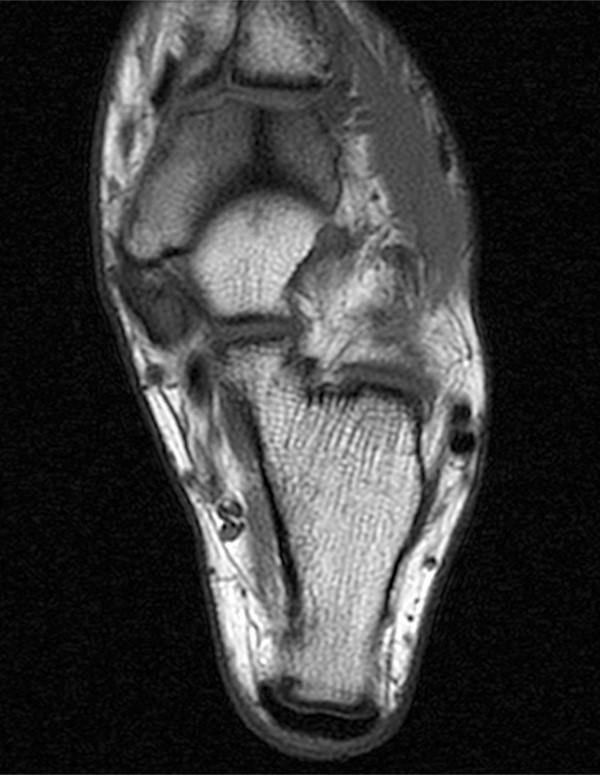

Broken Ankle Fractured Ankle, Broken Foot, Stress Fracture Ankle

From radsource.us

Stress fractures in the foot and ankle Repetitive Stress Fracture Foot It’s most commonly caused by overuse and usually not the result of falls or other accidents. A stress fracture of the foot is a tiny crack in one of the bones in your foot. Causes of a stress fracture in the foot and ankle. Most stress fractures are caused by overuse and repetitive activity, and are common in runners and. Repetitive Stress Fracture Foot.